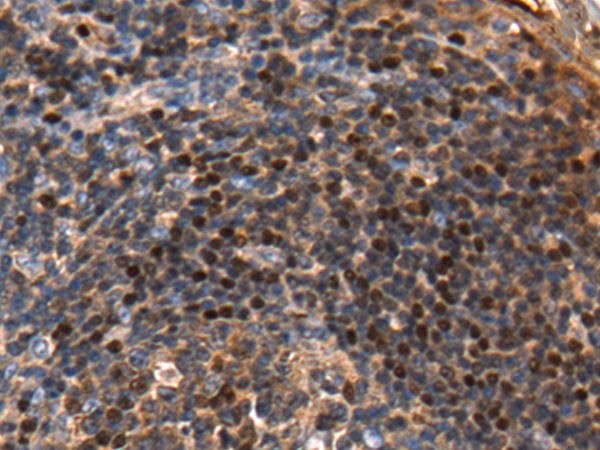

IHC positive control: |

Human tonsil |

IHC Recommend dilution: |

25-50 |